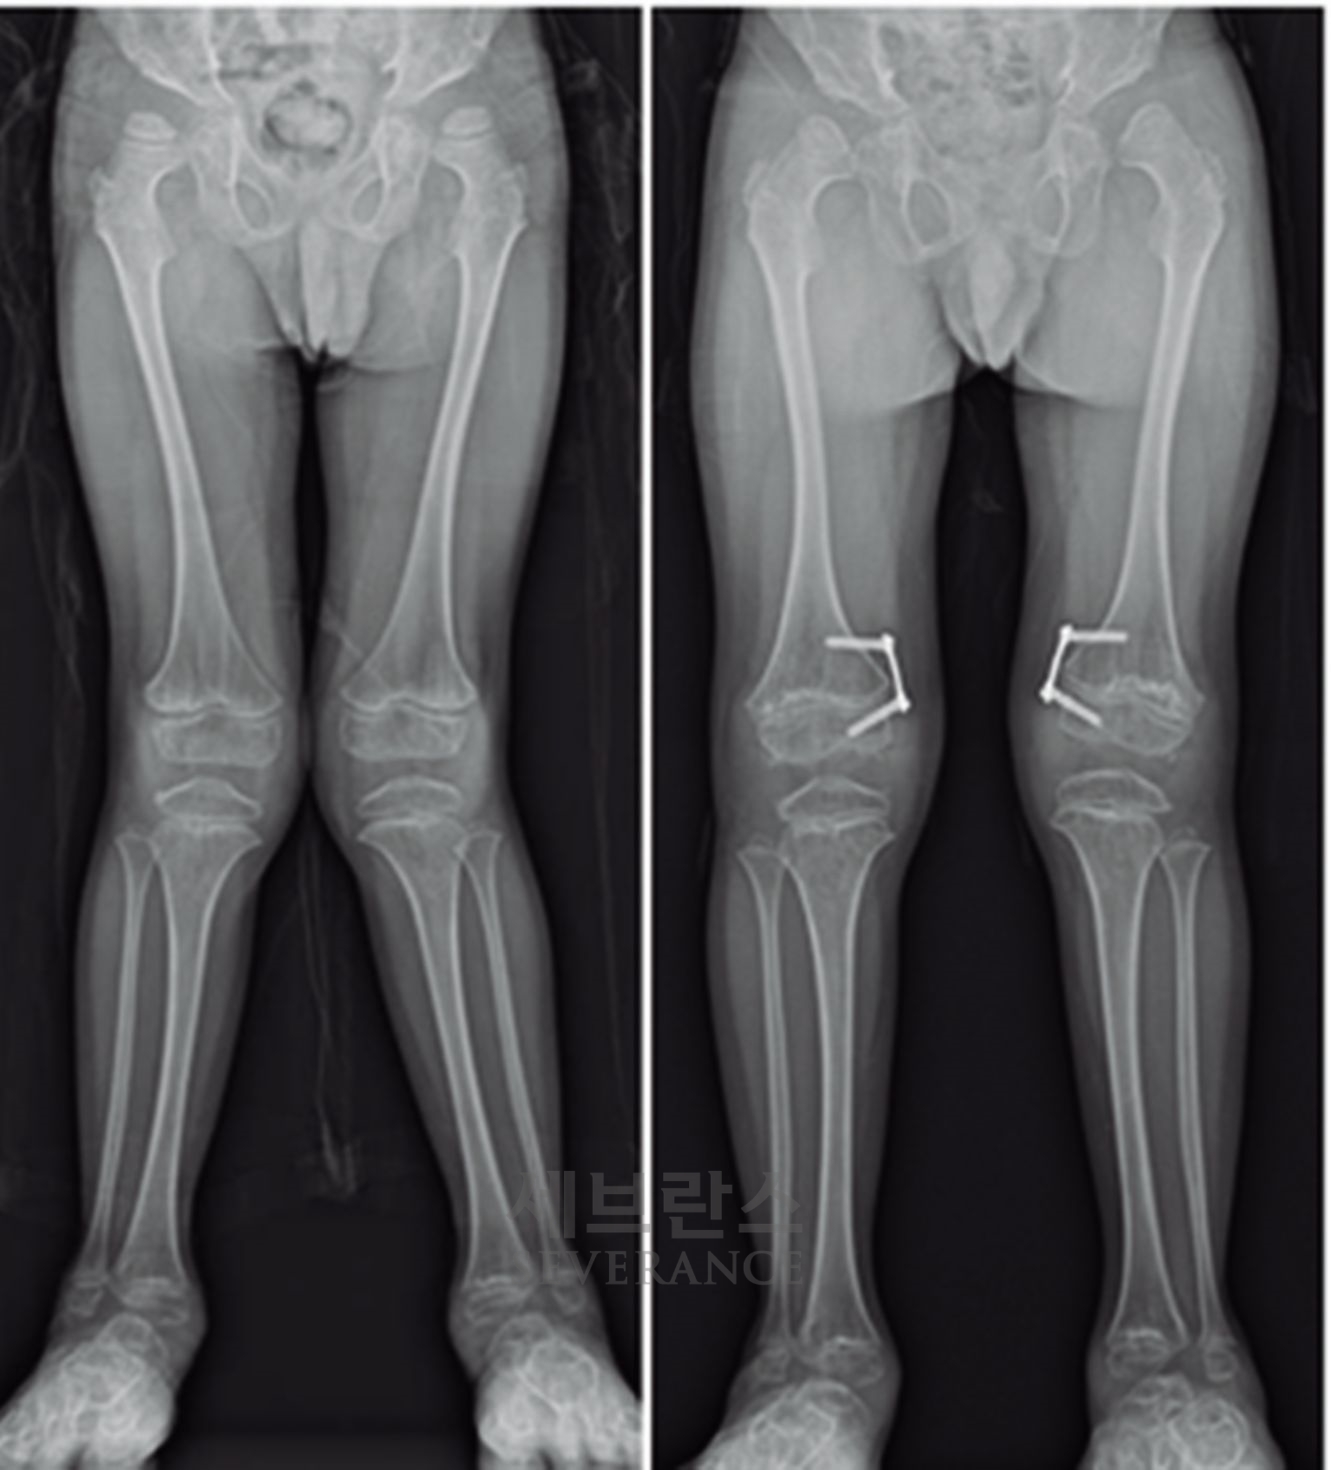

- 성장조절술

성장판이 열려 있는 아이에게 많이 사용되는 성장조절술은 한쪽 성장판의 성장을 일시적으로 억제해 시간이 지나면서 다리 길이나 각도가 서서히 교정되도록 하는 방법입니다. 일반적으로 심하지 않은 O다리나 X다리, 경미한 다리 길이 차이에 적용합니다. 흉터가 작고 회복이 빠르지만, 효과가 나타나기까지 시간이 필요하고 성장이 끝난 아이에게는 사용할 수 없습니다. 또 교정이 완료된 후에도 성장 과정에서 일부 각도가 다시 돌아오는 ‘성장 반동’ 현상이 나타날 수 있습니다. 따라서 성장판이 완전히 닫힐 때까지 정기적으로 추적 관찰을 받아야 합니다.

특발성 대사성 질환으로 인한 외반슬(X다리)에서 성장조절술을 시행한 환아성장판